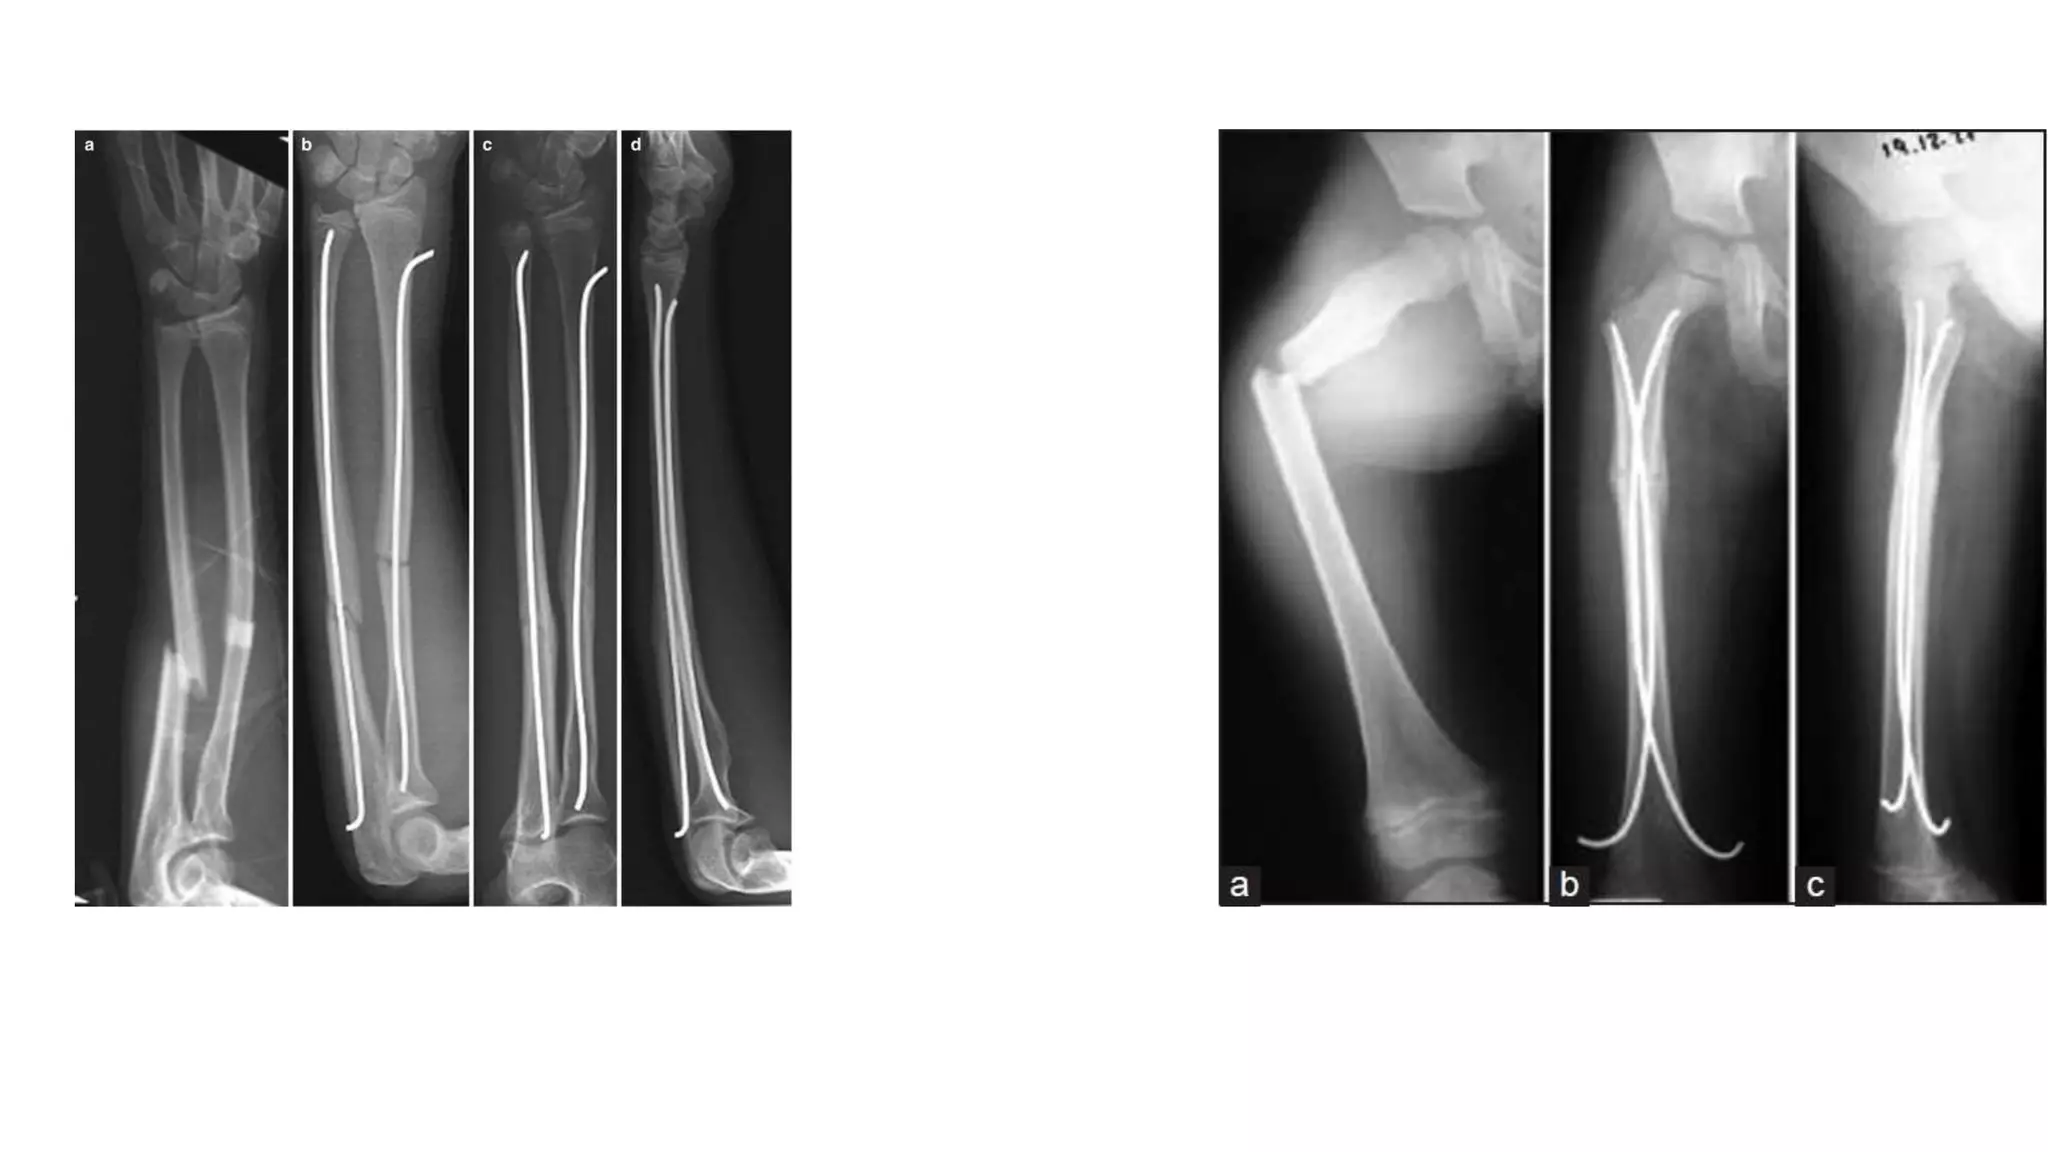

Elastic stable IM nailing

 Principle- three point fixation

 Callus formation

Closed reduction

Maintains length, rotation & alignment

Stainless steel or titanium alloys

 use-pediatric diaphyseal fracture (femur, radius, ulna, humerus)

Elastic stable IMnailing  Principle- three point fixation  Callus formation Closed reduction Maintains length, rotation & alignment Stainless steel or titanium alloys  use-pediatric diaphyseal fracture (femur, radius, ulna, humerus)